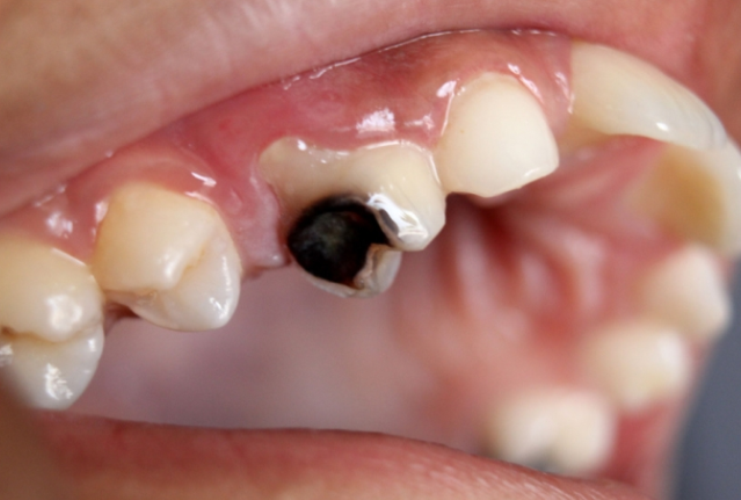

- Zuccheri Raffinati e Carico Fermentabile Elevato

L’introduzione massiva di saccarosio e carboidrati raffinati( snack, bevande zuccherate) ha determinato:

- Aumento della frequenza degli attacchi acidi

- Maggiore produzione di polisaccaridi extracellulari adesivi( glucani, appiccicosi) fanno da colla ai batteri.

- Biofilm più strutturato e resistente: la saliva penetra meno, gli acidi restano più a lungo e i batteri sono più protetti.

La frequenza di assunzione è spesso più dannosa della quantità assoluta. Ogni volta che si mangiano zuccheri il pH scende. Sotto 5,5 si ha un effetto demineralizzante.

Il saccarosio è cariogeno perché è sia substratoper la produzione di acidi sia precursore di polisaccaridi extracellulari che aumentano adesione e stabilità del biofilm.

Tuttavia, l’alimentazione moderna, industriale e processata:

- Aumenta la frequenza degli attacchi acidi

- Favorisce biofilm più patogeni

- Riduce la stimolazione fisiologica protettiva